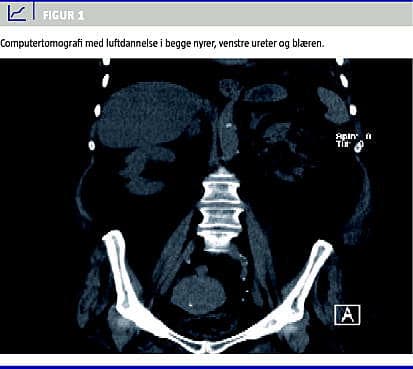

Hun havde ved indlæggelsen fire dages anamnese med abdominalsmerter og febrilia samt mikroskopisk hæmaturi, pyuri og akut nyreinsufficiens. Få timer efter indlæggelsen faldt blodtrykket til 68/38. Shocktilstanden udløste en akut computertomografi (CT) af abdomen, som viste luftdannelse i parenkymet i begge nyrer, venstre ureter og blæren (Figur 1 ). Der fandtes plasmakreatinin på 268 mikromol /l, metabolisk acidose og tegn på svær infektion (C-reaktivt protein (CRP): 270 mg/l og trombocytopeni 108 mia/l).

Summary Renal and urethral gas production as a complication to infection of the urinary tract Ugeskr Læger 2010;172(35):2389-2390 Emphysematous pyelonephritis (EPN) is a bacterial infection characterised by gas production in the renal parenchyma. We present a case with EPN caused by Klebsiella pneumoniae sepsis. The 74-year-old woman was admitted in septic shock. An acute computed tomography revealed gas bubbles bilaterally in the renal parenchyma, left urethra and bladder. Treatment consisted of three types of antibiotics and intravenous fluids. She was discharged two months later without need for surgical treatment or haemodialysis despite the seriousness of her initial condition.